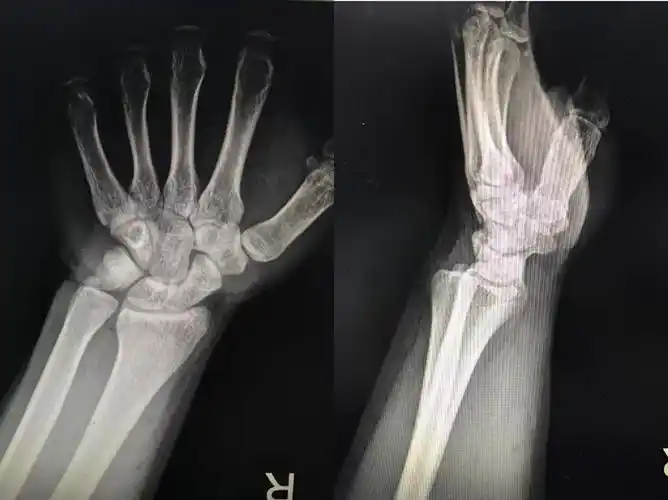

下尺桡关节脱位一例

桡骨远端骨折伴腕关节脱位

桡骨远端骨折合并下尺桡关节脱位